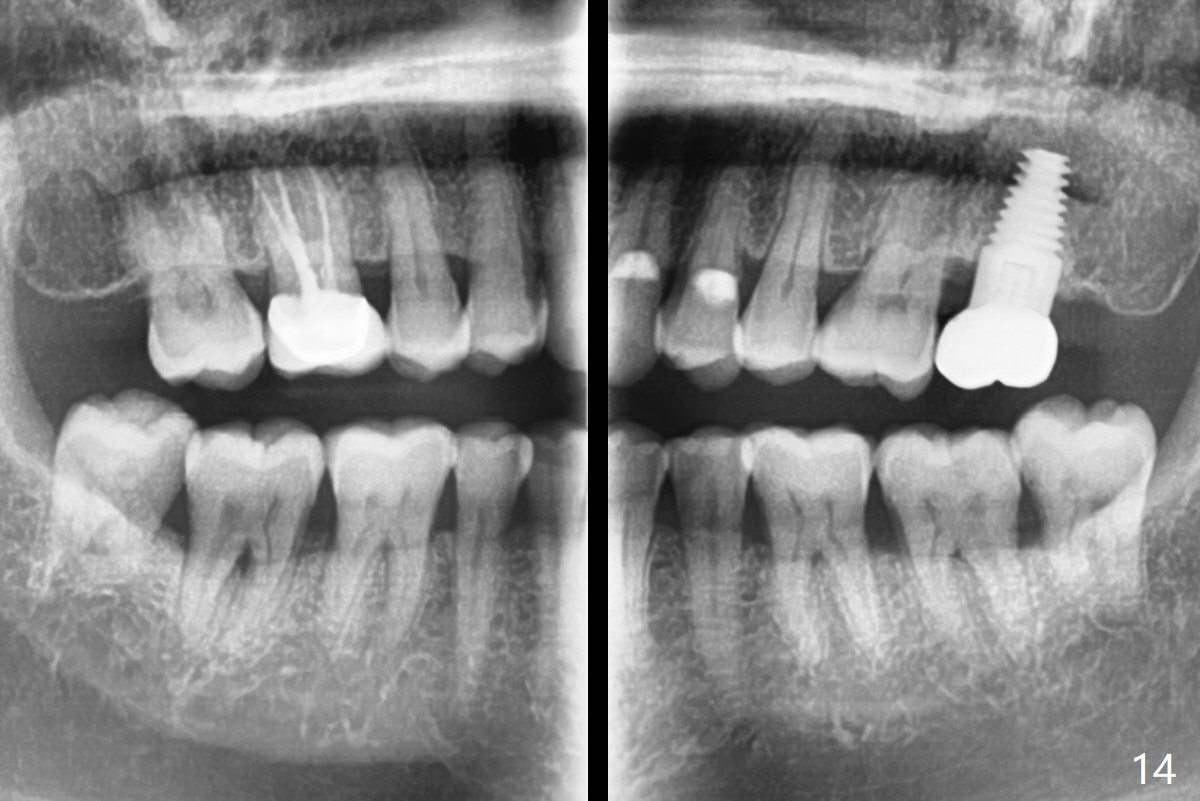

There is no bone loss 17 months post cementation (Fig.12). The patient reports that he has to keep cleaning well to prevent discomfort locally. Clinically, the gingiva is healthy around the implant crown. No bone loss is around the implant 3 years 8 months post cementation (Fig.13), but the natural teeth are not so fortunate (Fig.14).